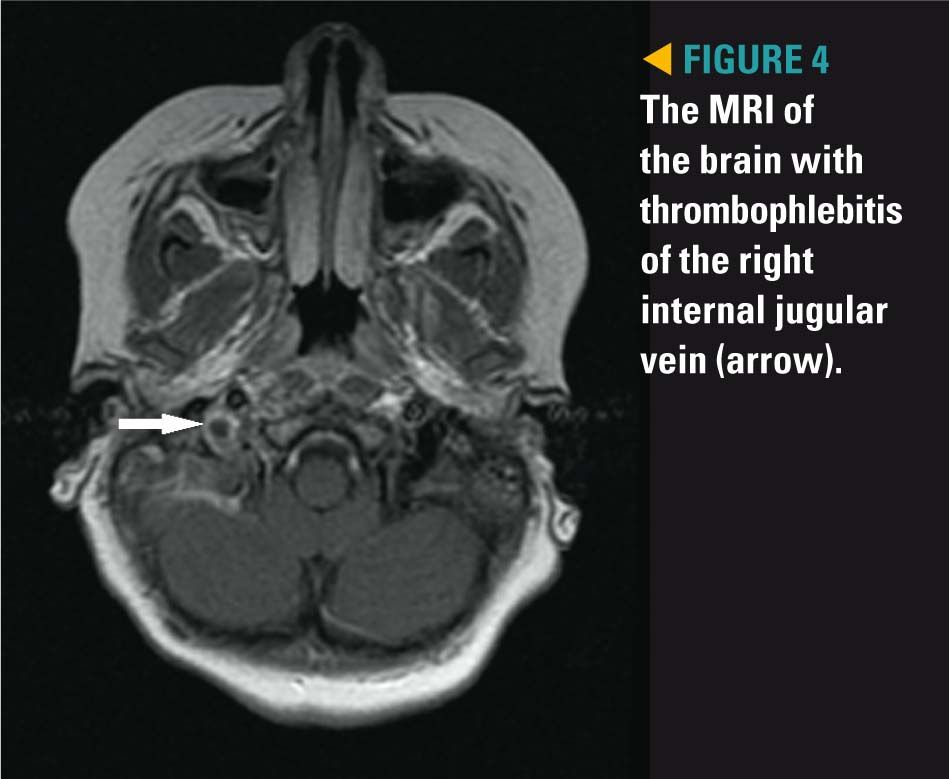

Because of intermittent low-grade fevers (100.4°F to 101.8°F) for 5 days despite drainage of the right ankle and foot abscesses, wide-spectrum IV antibiotics, and persistent pain of right ear and neck, a computed tomography (CT)scan of the temporal bones and an MRI of the brain and neck were obtained. The CT showed right otomastoiditis (Figure 2) and thrombophlebitis of the right sigmoid sinus, jugular vein, and transverse sinus (Figures 3 and 4). Otolaryngology took the patient to the operating room for a right myringotomy with pressure equalization tube placement, right mastoidectomy, and facial nerve monitoring. To decrease the risk of idiopathic intracranial hypertension resulting from cerebral venous thrombosis, Hematology recommended starting enoxaparin.